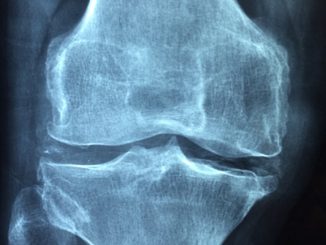

rodillas

La clave para recuperar la movilidad en las rodillas dañadas

Las lesiones de menisco representan una de las causas más frecuentes de dolor y limitación en las rodillas, afectando tanto a deportistas como a personas […]